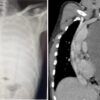

सफलता: फेफड़े में था सवा तीन किलो का ट्यूमर, एम्स के चिकित्सकों ने बचाई जान…

June 21, 2024ऋषिकेश। समय पर इलाज शुरू होने से गम्भीर बीमारी से ग्रस्त व्यक्ति के जीवन को भी...